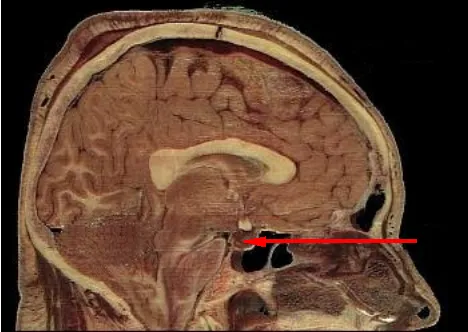

The oxt is then released into your blood stream, as deemed "necessary" by the vagueries of the things that happen to you and the commands of your brain. Oxt is released from your pituitary gland, which is roughly where the arrow in the much more disconcerting picture to the left is pointing.